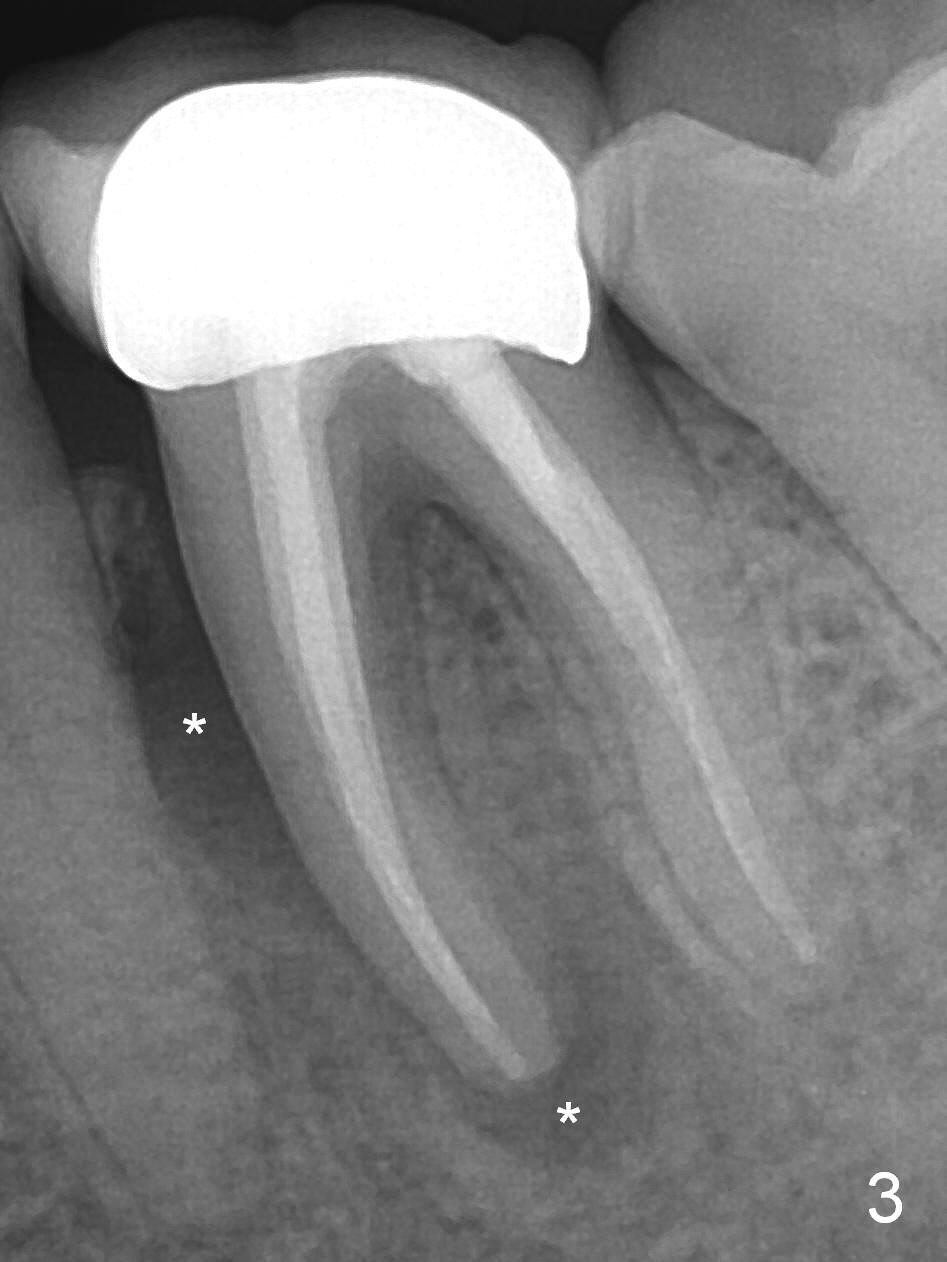

A 59-year-old woman had root canal therapy for the tooth #19 10.5 years ago (Fig.1 (red dashed line: the superior border of the Inferior Alveolar Canal). Two years later there was apparent periapical radiolucency with the distal root (Fig.2 *). The tooth remains asymptomatic until the last six months. There are 2 fistulae associated with the tooth: mesiolingual and buccal furca. Radiogra-phically, there are 2 radiolucent lesions: mesial and apical to the mesial root (Fig.3 *). If a 16 mm implant is placed, there will be approximately 5 mm apical bone (Fig.4); 7 mm for a 18 mm implant. The bone height is 25 mm (Fig.6). Therefore, once initial osteotomy is established with a 13 mm long drill with PA confirmation, the osteotomy is extended to its depth with 1.5x21 mm drill (Fig.5). After socket treatment with Metronidazole gauze with Epinephrine (1: 50,0000), take PVS impression of the socket to catch the large mesial defect. A fair amount of allograft and Osteogen is expected. It has been 9 months since last visit. Retake PA before surgery. If the mesial defect enlarges, start osteotomy in the distal slope of the septum.